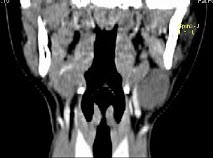

- 单项选择题女,16岁,发现左颈部肿块两年,CT如图所示,最可能的诊断为()。

D、左侧鳃裂囊肿

- D